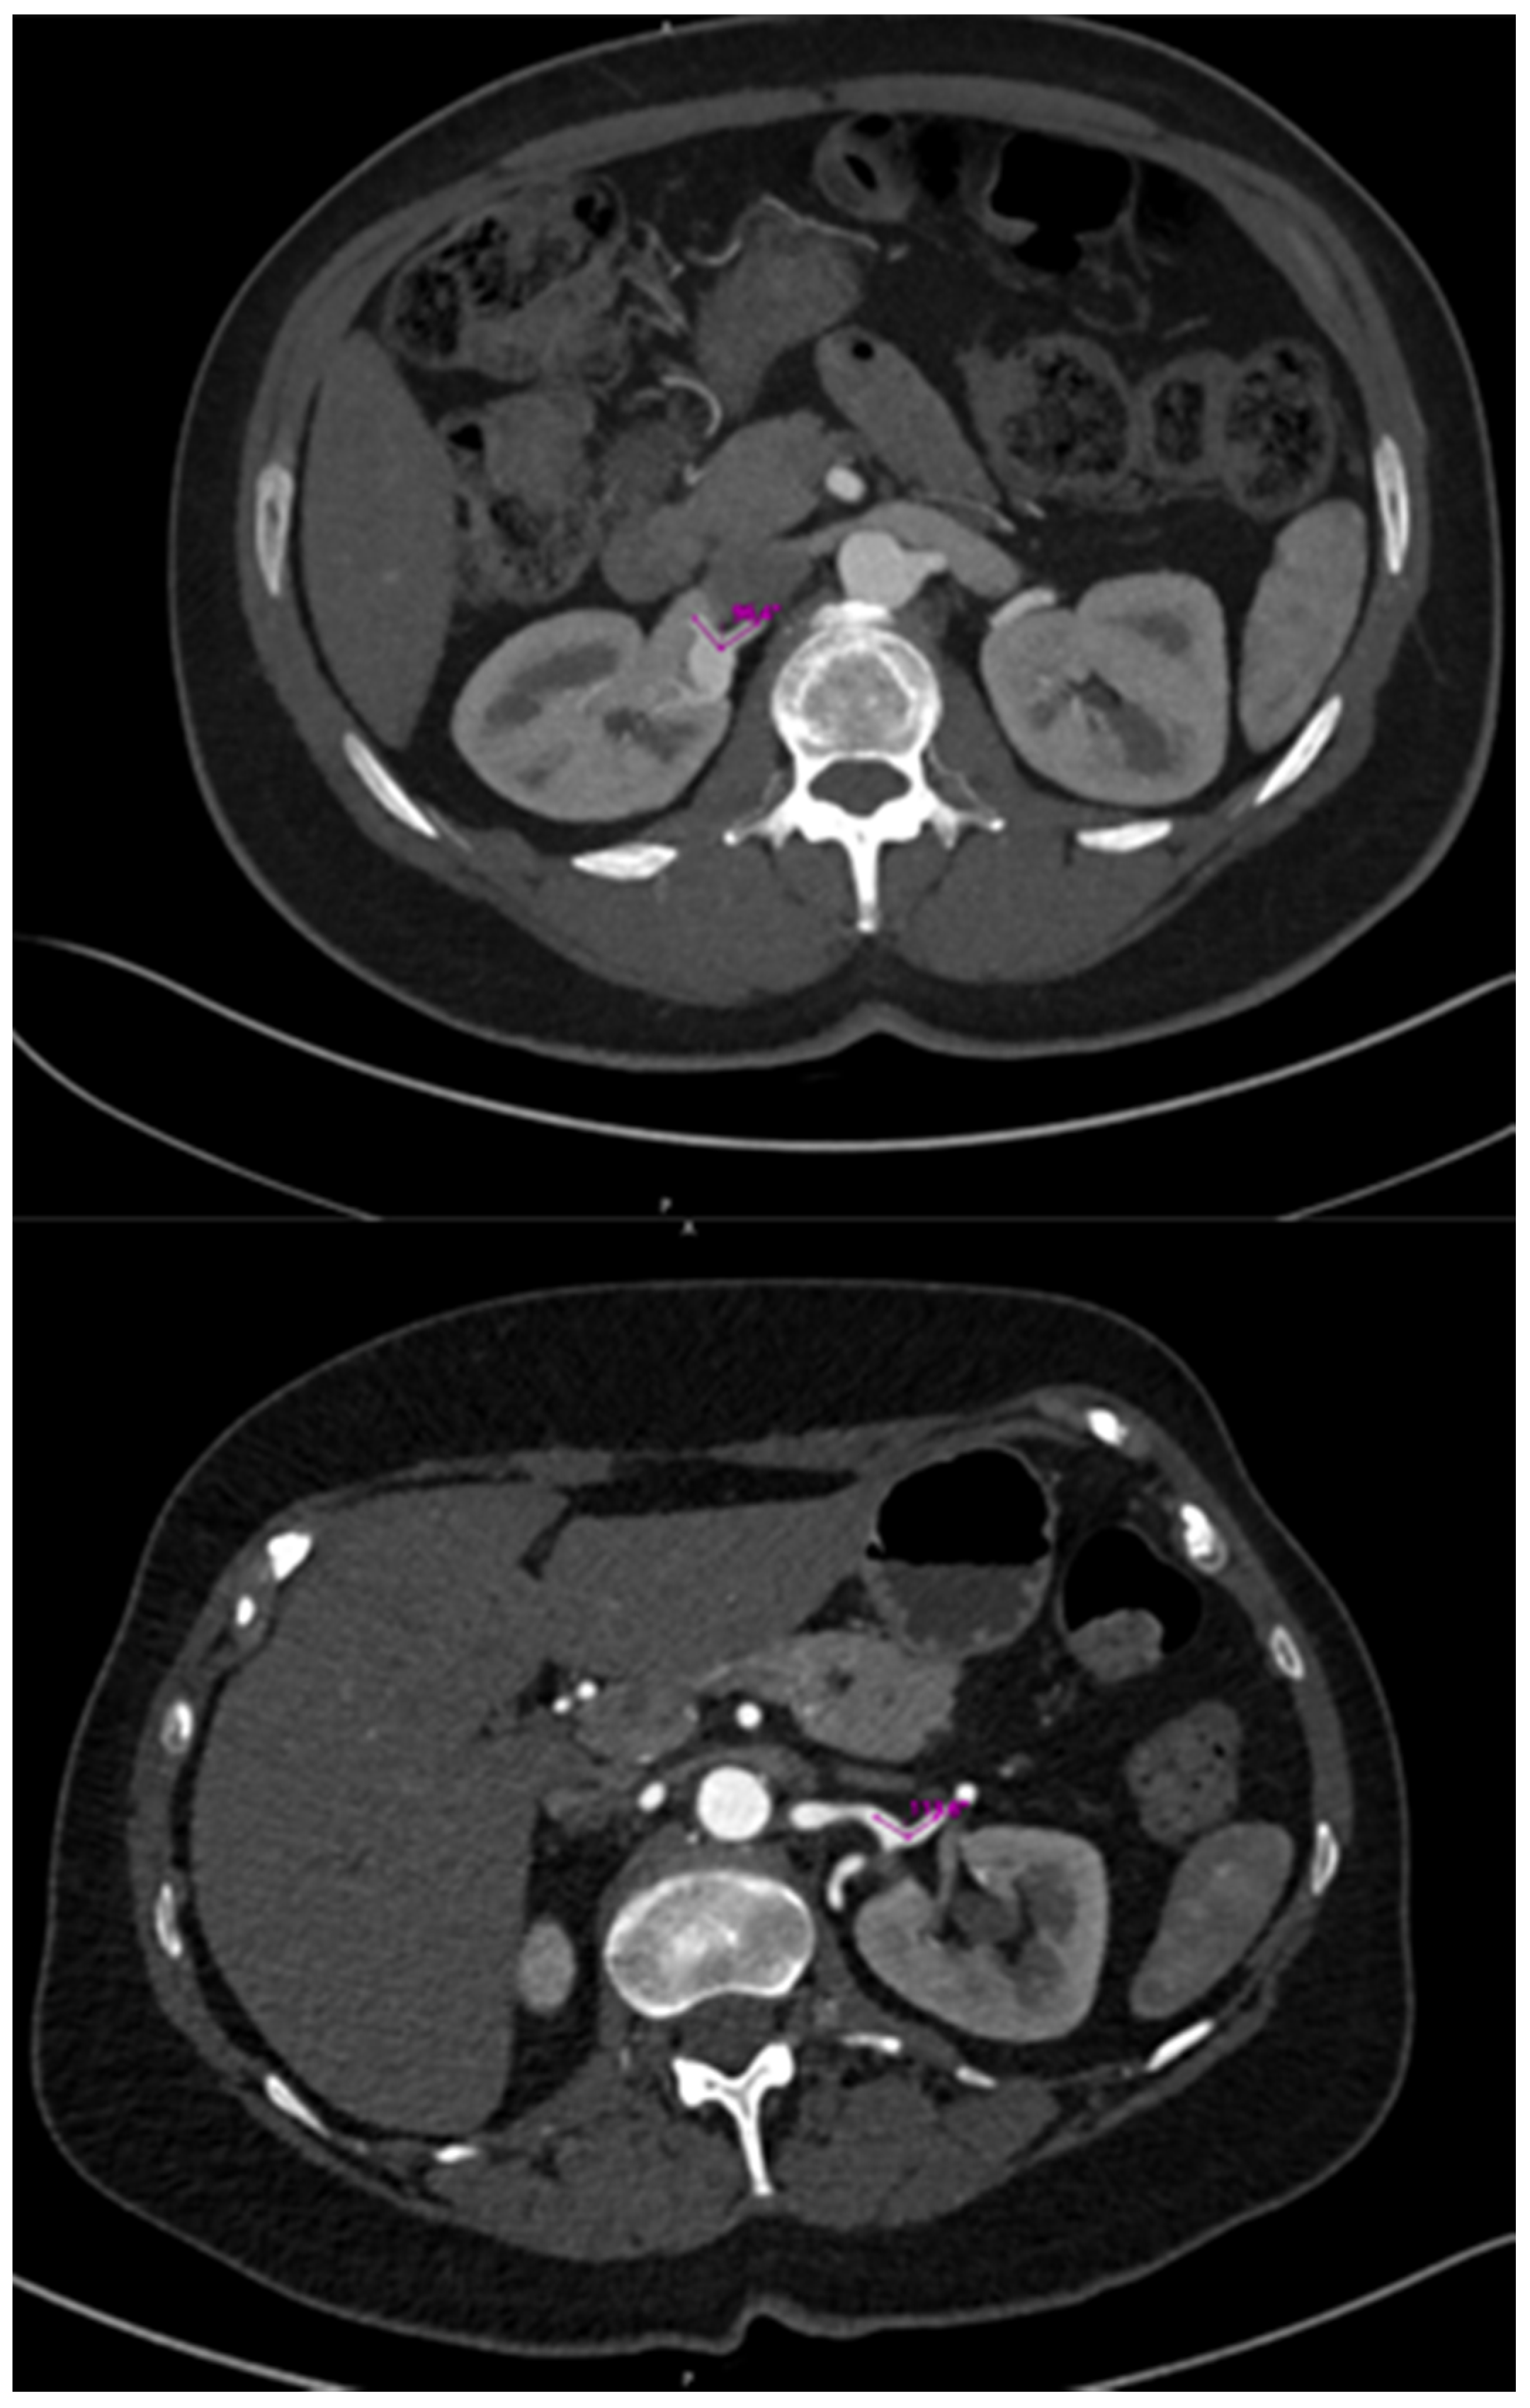

3.2. Imaging Findings